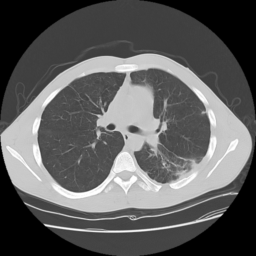

![]() |

| (a) | (b) | (c) | (d) |

Unsupervised Categorization: Our category discovery clusters are generally visually coherent within the cluster and size-balanced across clusters. However, image clusters formed only based on text information (of radiology reports) are highly unbalanced [49], with three clusters inhabiting the majority of images. Note that our method imposes no explicit constraint on the number of instances per cluster. Fig. 6 shows sample images and their top-10 associated key words from two randomly selected clusters (more results are provided in the supplementary material). The LDPO clusters are found to be clinically or semantically related to the corresponding key words, which describe presented anatomies, pathologies (e.g., adenopathy, mass), their associated attributes (e.g., bulky, frontal) and imaging protocols or properties.

The category discovery clusters employing our LDPO method are found to be more visually coherent and cluster-wise balanced in comparison to the results in [49] where clusters are formed only from text information ( radiology reports). Fig. 7 Left shows the image numbers for each cluster from the AlexNet-FC7-Topic setting. The numbers are uniformly distributed with a mean of 778 and standard deviation of 52. Fig. 7 Right illustrates the relation of clustering results derived from image cues or text reports [49]. Note that there is no instance-balance-per-cluster constraints in the LDPO clustering. The clusters in [49] are highly uneven: 3 clusters inhabit the majority of images. Fig. 6 shows sample images and top-10 associated key words from 5 randomly selected clusters (more results in the supplementary material). The LDPO clusters are found to be semantically or clinically related to the corresponding key words, containing the information of (likely appeared) anatomies, pathologies (e.g., adenopathy, mass), their attributes (e.g., bulky, frontal) and imaging protocols or properties.